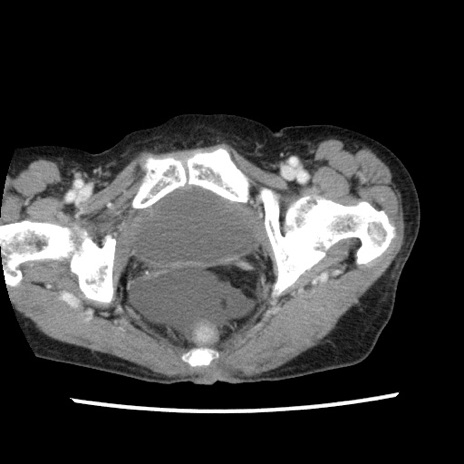

矢状断像

【症例】80歳代女性

【主訴】腹痛

【現病歴】8時間前から腹痛あり来院。

【既往歴】糖尿病、脂質異常症、子宮体癌にて子宮全摘術

【身体所見】意識清明・会話良好だが腹痛で苦悶様、全腹部にわたって反跳痛と圧痛あり

【データ】WBC 13600、CRP 0.14、LDH 224、CK 90